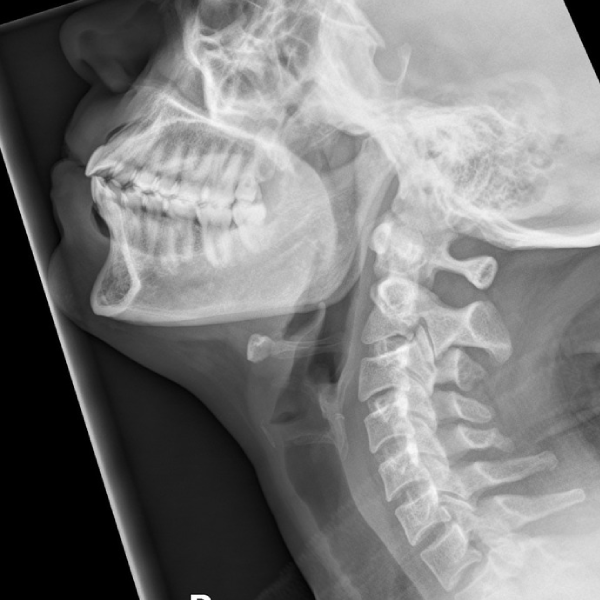

Learn the bony anatomy then test yourself

Learning mode: Hover over the name tags to highlight the relevant anatomy. Once you're ready, head to study mode.